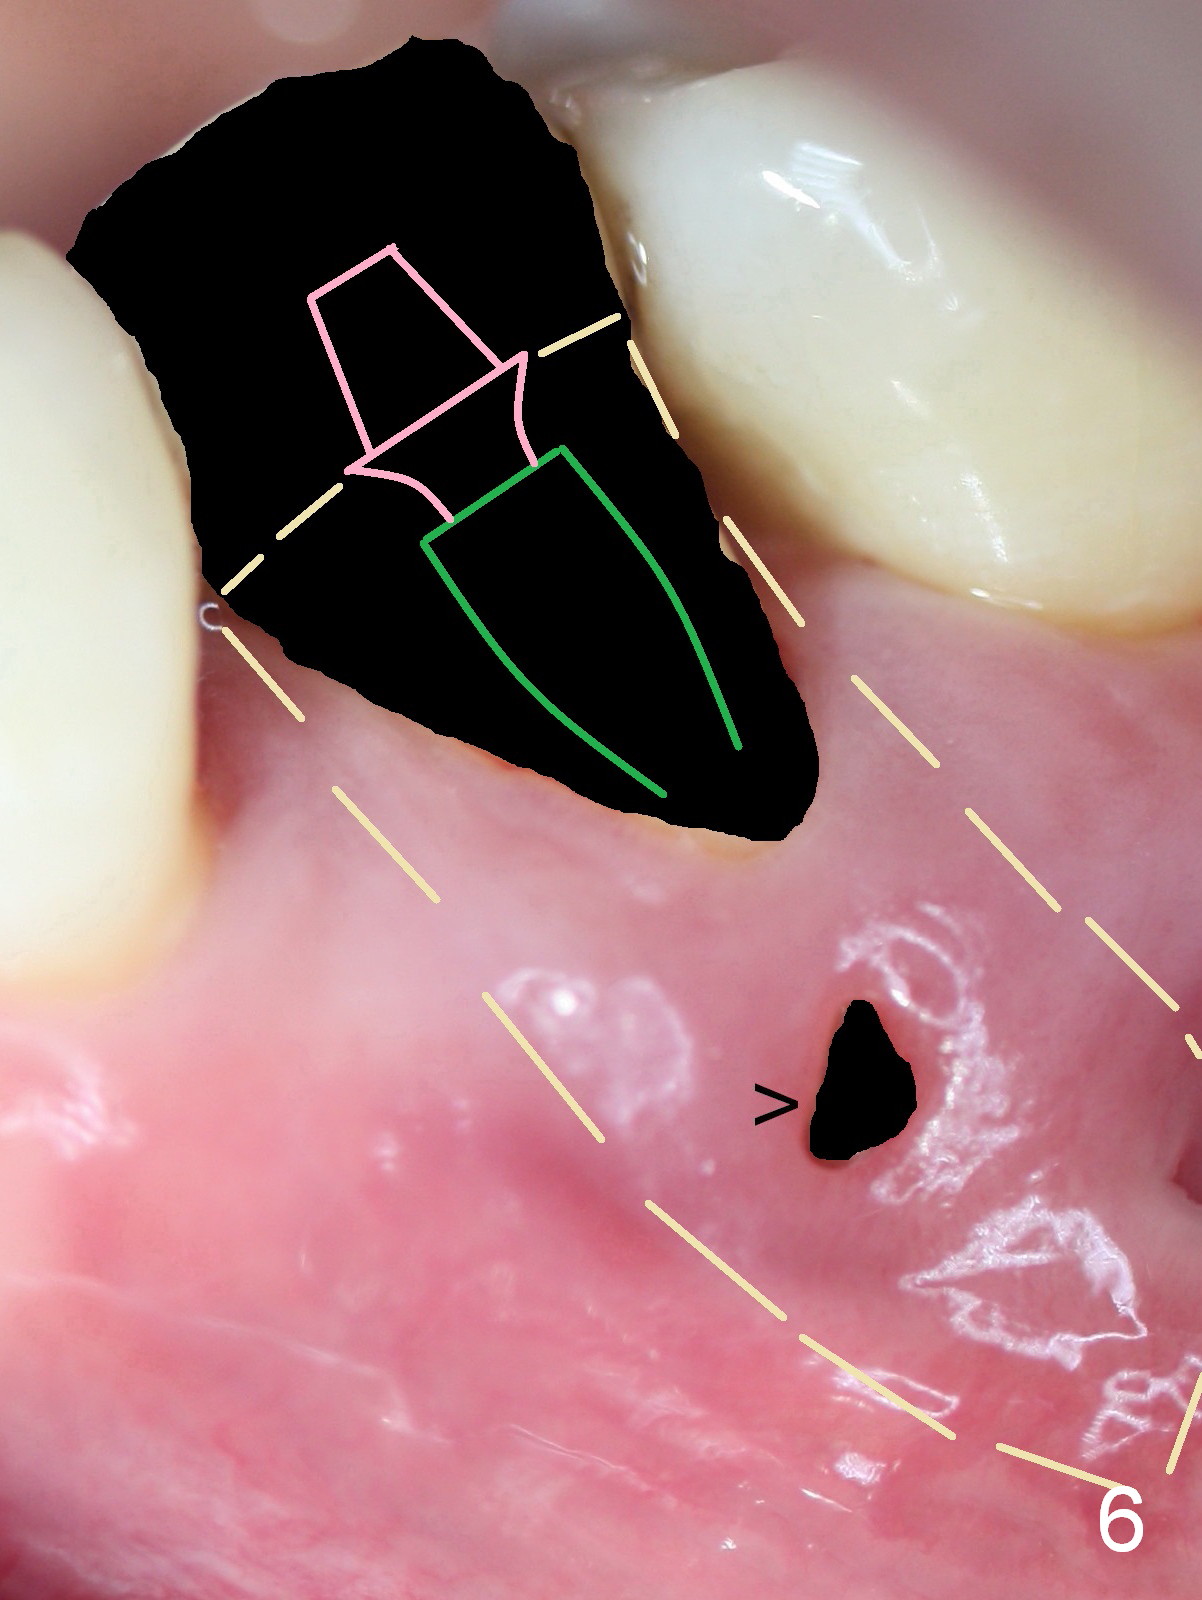

A 45-year-old man (JT) has endo failure at #20 with fenestration (Fig.1,2 black >) and fistula (white <). Insertion of a Gutta Percha at the fistula (Fig. 3 <; PA taken 2 years ago) indicates that the infection is dervied from the apex of the tooth #20. The socket will be soaked with 2% Xylo, 1:50,000 Epinephrine gauze. A 4.5x17 mm tissue-level (Fig.4) or 14 mm bone-level implant is placed as lingual as possible (Fig.5 green). If primary stability is achieved, an abutment is placed (pink). A large piece of resorbable membrane is used to cover the buccal defect (including buccal recession, fenestration and fistula (Fig.6 yellow dashed line). Two small pieces of non-resorbable membrane are placed to cover the gingival recession and the fenestration (Fig.7 white dashed line, buried underneath the edge of the gigniva). Then place bone graft buccally. Place a small piece of gauze (one layer) or plastic (from Tatum implant bag) over the 2nd membrane over the gingival recession and fabricate an immediate provisional. When the acrylic is partially set, remove the gauze or plastic from the provisional. After trimming and polishing, the provisional is cemented to securely keep the 2nd membrane in place. When the wound is healing and the 2nd membrane is stable, trim the buccal extension of the provisional. It is expected that the buccal hard and soft tissue will regenerate over the implant.